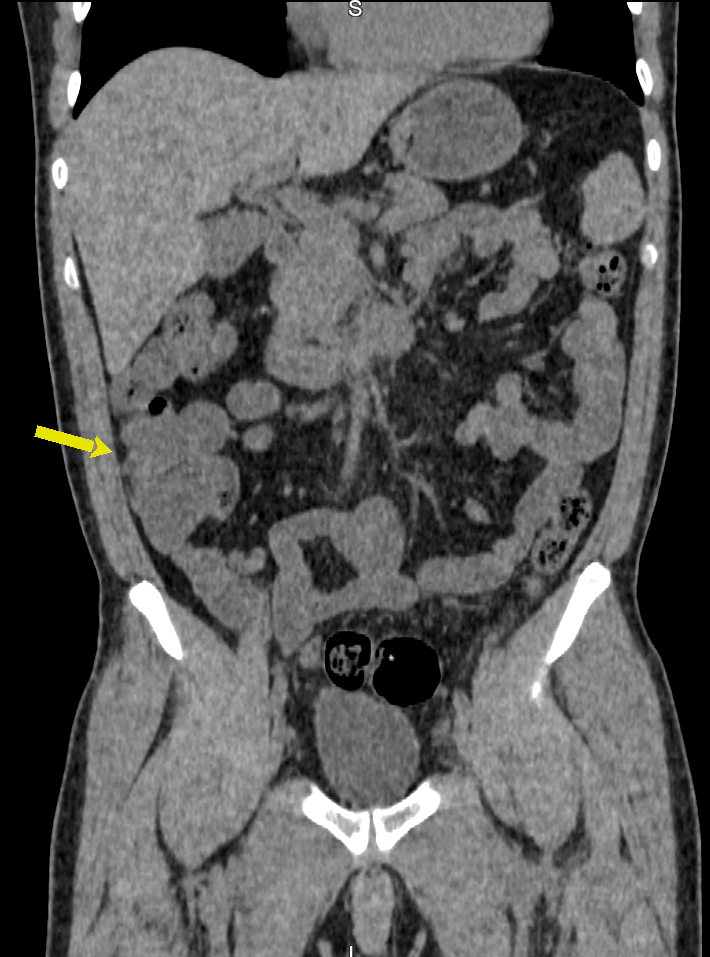

A Enterografia por Tomografia Computadorizada é um exame que estuda o intestino delgado, permitindo diagnóstico de diversas doenças que afetam este órgão, como a Doença de Crohn. O exame também é conhecido como enterotomografia. Assemelha-se à tomografia computadorizada tradicional com contraste.

A Enterotomografia difere da TC convencional de abdômen pela utilização de grandes volumes de contraste oral e cortes finos, com reconstruções multiplanares. As principais indicações são para as seguintes situações: avaliação de sangramento gastrointestinal obscuro, diagnóstico e acompanhamento de doença inflamatória intestinal, especialmente a doença de Crohn, e pesquisa de neoplasias intestinais.